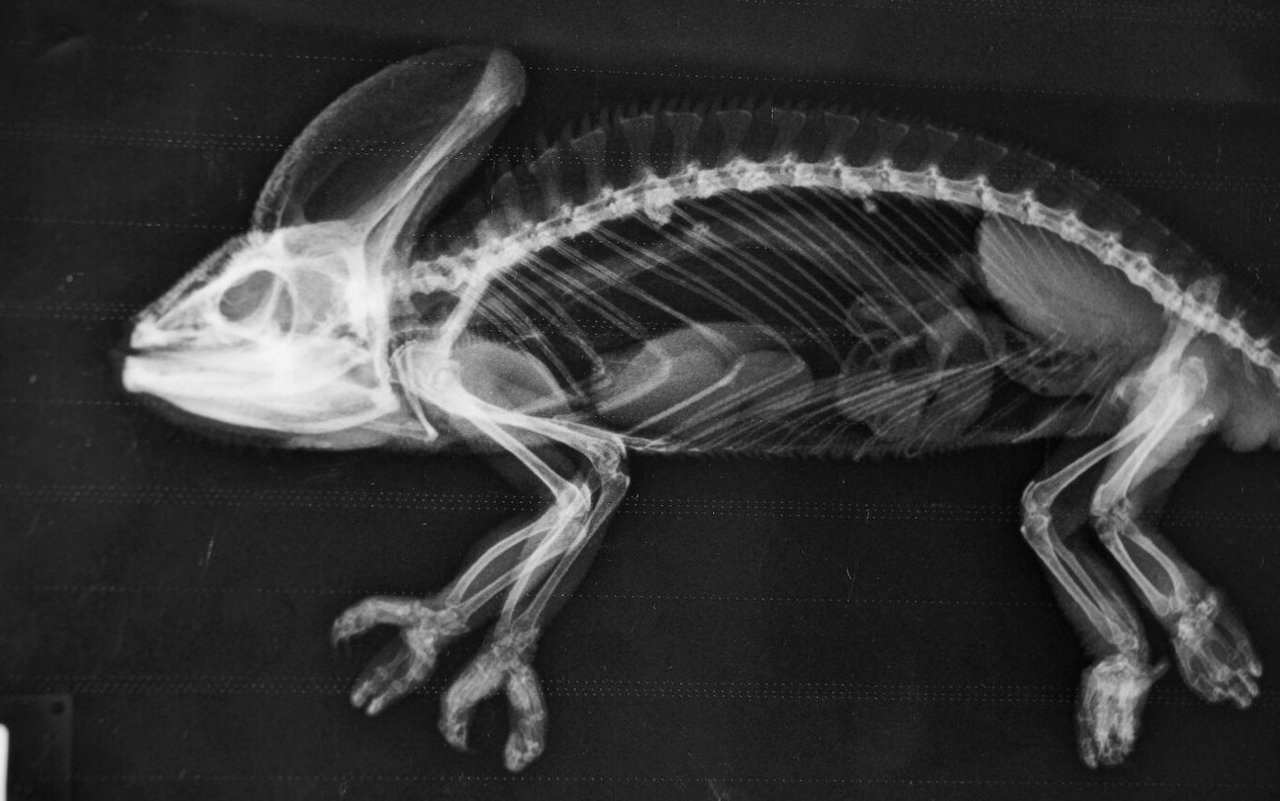

Erstaunlich, das Gerippe eines Seepferdchens! Wie ein Kunstwerk zeigen sich die Knochen, die der Bezeichnung Knochenfische alle Ehre machen. Wundersam wirkt das filigrane Schlangenskelett. Im Röntgenraum der Tierklinik im Basler Zoo wird rasch klar, wie komplex die Arbeit eines Zootierarztes ist. Er muss die Röntgenbilder zahlreicher verschiedener Arten interpretieren. Doch die Schwierigkeit beginnt schon vorher. Wie bekommt man Tiere, vom Seepferdchen bis zum Geparden, auf den Röntgentisch?

Dr. Christian Wenker ist froh über die Möglichkeit, Tiere röntgen zu können. Der leitende Veterinär im Basler Zoo erklärt: «Dank dem bildgebenden Verfahren haben wir in der Zootiermedizin ein rasches Resultat.» Bei Blut- und Kotuntersuchungen müsse bis am nächsten Tag gewartet werden. Schnelles Handeln ist in der Zootiermedizin wichtig. Zeigen Tiere Krankheitssymptome, liegt ein gravierendes Problem vor. Sie verbergen Unwohlsein, denn in der Natur werden schwächelnde Tiere durch Feinde eliminiert.